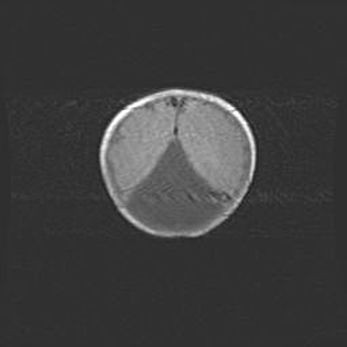

Мальформация Денди-Уокера. Киста задней черепной ямки.

Агенезия мозолистого тела.

Возраст: 2,5 месяца

Вес: 2420 г

Пол: женский

Окружность головы: 37 см

Срок гестации: 32 недели

Мальформация Денди—Уокера — редкий вид патологии ЦНС, представляющий собой врожденный порок развития каудального отдела ствола и червя мозжечка, ведущий к неполному раскрытию срединной (Мажанди) и латеральных (Лушка) апертур IV желудочка мозга. Для этогно синдрома характерна триада симптомов: гипотрофия червя мозжечка и/или полушарий мозжечка, кисты задней черепной ямки, гидроцефалия различной степени. В 70% случаев порок сочетается и с другими аномалиями головного мозга, в частности с агенезией мозолистого тела.